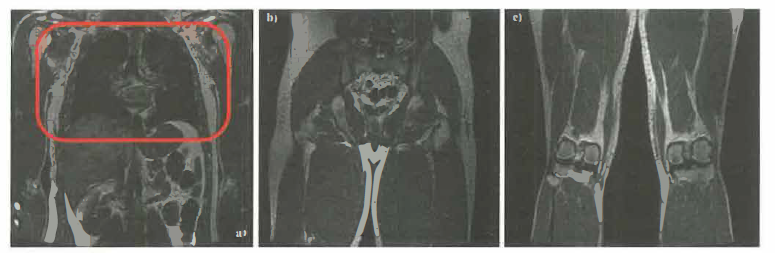

La flessibilità dei parametri di sequenza permette pesature differenti (T₁, T₂, densità protonica) e applicazioni avanzate: diffusione (DWI), perfusione, imaging funzionale BOLD, angiografia senza mezzo di contrasto, e spettroscopia ¹H‑MRS per metaboliti selezionati. Esempi di immagini cliniche sono illustrati in (Figura 07.28-23); un sistema RM a corpo intero è mostrato in (Figura 07.28-24).

La codifica spaziale si ottiene applicando gradienti di campo magnetico, che rendono la frequenza di risonanza funzione della posizione. Variando nel tempo i gradienti lungo le tre direzioni (x, y, z), si selezionano fette e si attribuisce la codifica di fase e di frequenza ai segnali, discriminando i contributi dei diversi volumetti (Figura 07.28-21). L’insieme delle misure, interpretabile come una collezione di proiezioni della stessa grandezza fisica a più angoli e configurazioni (Figura 07.28-22), consente la ricostruzione della mappa di densità protonica e dei parametri di rilassamento. Poiché la sensibilità è principalmente verso i protoni, le immagini RM riflettono in larga misura la distribuzione dell’idrogeno, abbondante nelle molecole d’acqua e nei lipidi.